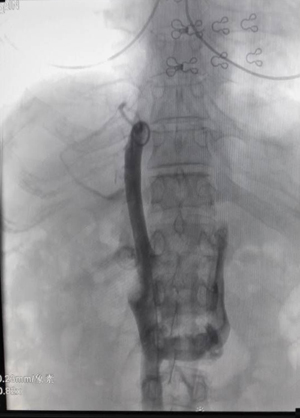

征得患者家属同意后,19时10分,患者曹智即被送入介入手术室,全脑血管造影结果证实为脑基底动脉顶端动脉瘤破裂,马修尧主任立即向患者家属解释患者此次颅内出血原因为颅内动脉瘤破裂所致,病情垂危,并将手术方式、手术风险、术后治疗、初步治疗费用等向患者家属进行分析、说明。患者家属经短暂商量后表示尽全力抢救,马修尧主任带领他的团队随即为曹智实行脑动脉瘤血管内介入栓塞术。从股动脉穿刺置入的微导管内用弹簧圈成功将动脉瘤进行栓塞。栓塞后再次造影,动脉瘤已经不见踪影。

治疗前

治疗后